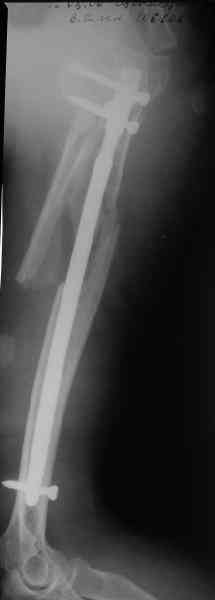

Добрый вечер!

Приложение как пример.

Консервативно он уже лечился до этой операции в течение трёх с половиной месяцев.

А именно такой вариант операции выбран из экономических соображений.

вообще, торчашие в субакромиальное пространство шипы оставляют неизгладимое впечатление. Не думаю, что таким имплантом есть смысл гордиться